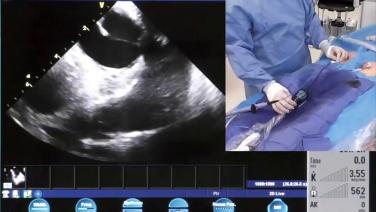

Identifying Left Atrial Anatomy using Intracardiac Echo for Transseptal Puncture with James Brian Deville, MD